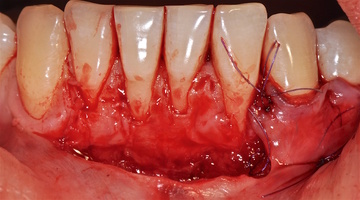

1. Генерализованные рецессии в области нижней челюсти оперировались в один этап все 12 зубов, фронтальный участок с аутотрансплантатом от 3.2 до 4.2 зубов. А дистальные участки от 3.6 до 3.3 и от 4.6 до 4.3 зубов с использованием пластического материала ТМО (dura mater) (рис. 4а-з).

4. Этапы хирургического лечения рецессий десны на нижней челюсти

3.2-4.2 зубы были прооперированы методом, сочетающим вестибулопластику с одновременным увеличением ширины и толщины прикрепленной десны при помощи свободного десневого аутотрансплантата (операция Bjorn, 1963 г.).

1. Подготовка принимающего ложа. Включает в себя формирование полнослойно-расщепленного слизисто-надкостничного лоскута (полнослойного в области зенитов рецессий, расщепленного билатерально области рецессии десны), рассечение и отслаивание слизисто-мышечных волокон вестибулярно ниже мукогингивальной границы, деэпителизация межзубных сосочков.

2. Обработка поверхностей корней зубов. Включает ультразвуковую обработку скейлером для очищения от минерализованных зубных отложений и мягкого зубного налета, экспозицию геля ЭДТА 17% в течение двух минут, механическое удаление слоя бесклеточного цемента импрегнированного микроорганизмами зоноспецифическими кюретами, полировку пародонтологическими борами («фасолька» и «обратный треугольник»).

3. Получение аутотрансплантата: начинается с определения толщины донорской зоны и замеров размера будущего трансплантата. Зона забора от второго премоляра до третьего моляра верхней челюсти. Глубина погружения брюшка скальпеля 2 мм, далее трансплантат оптимизируют — деэпителизируют по периметру.

4. Затем проводиться позиционирование аутотрансплантата в области рецессий и принимающего ложа двумя-тремя узловыми швами; после аутотрансплантат стабилизируют прижимающими двумя-четырьмя матрасными крестообразными швами, что позволит плотно прижать аутотрансплантат и избежать образования «мертвых» зон для питания аутотрансплантата.